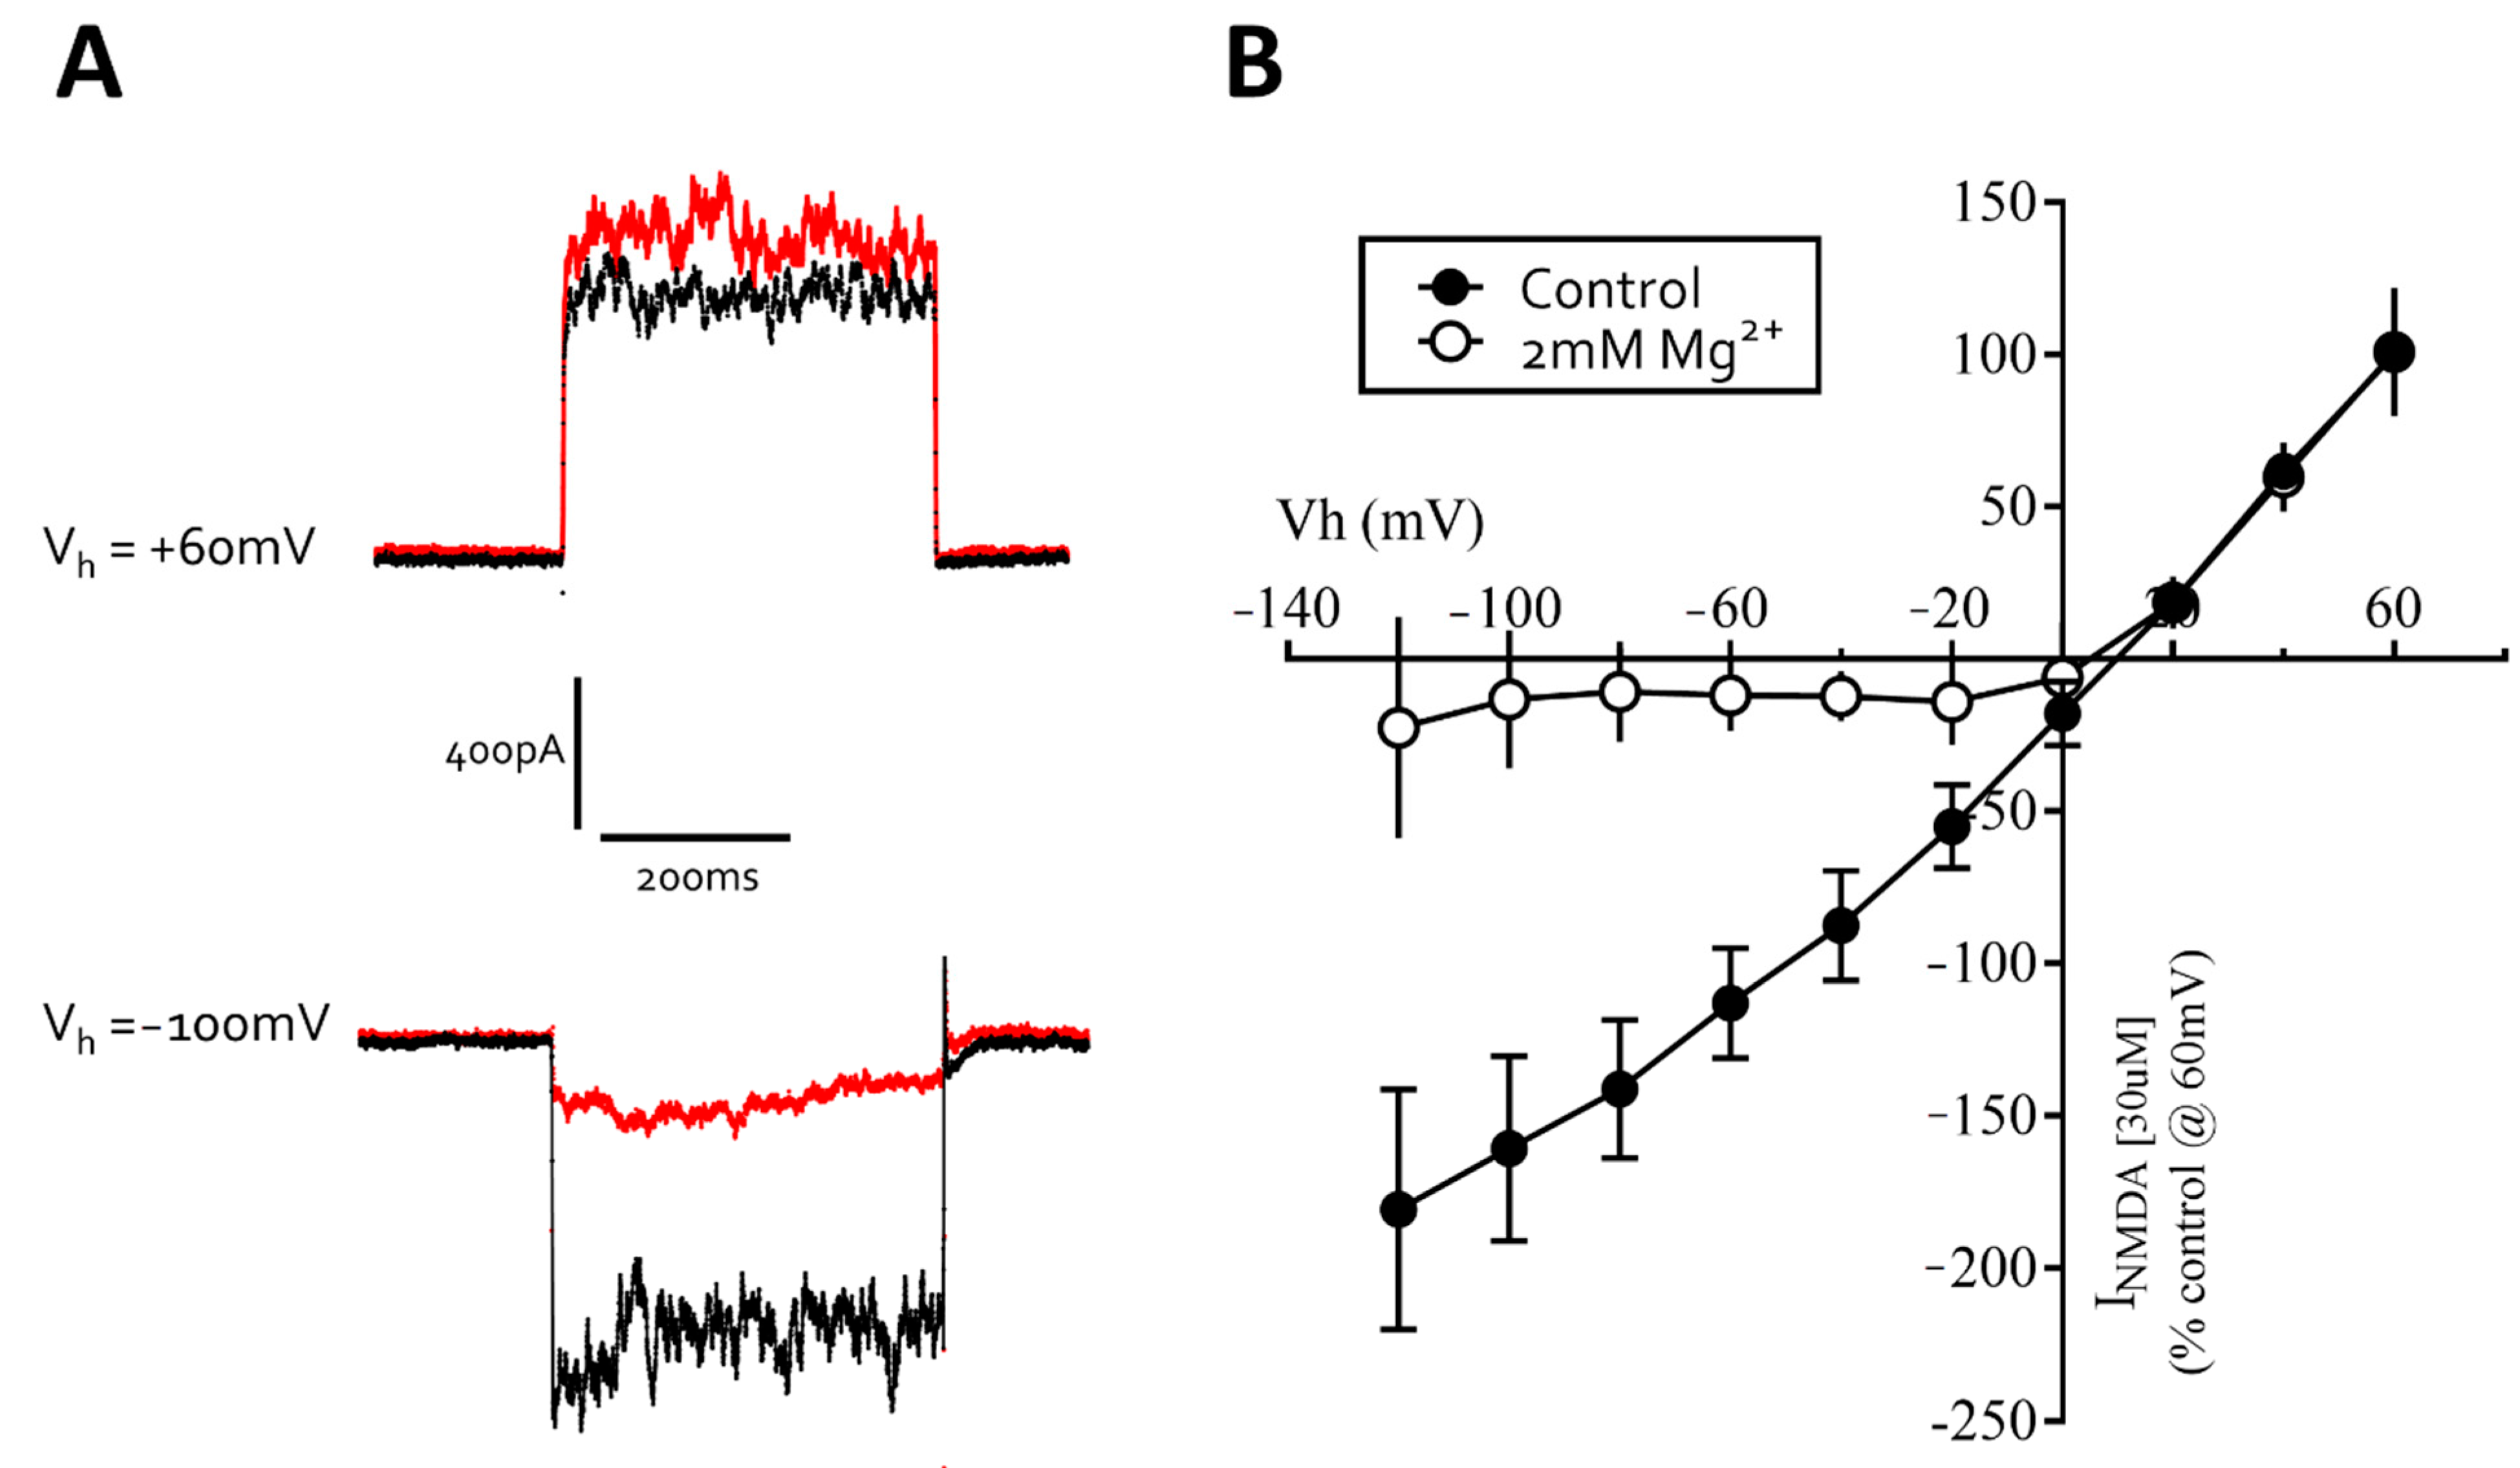

3.3. Excitatory Ligand-Gated Currents